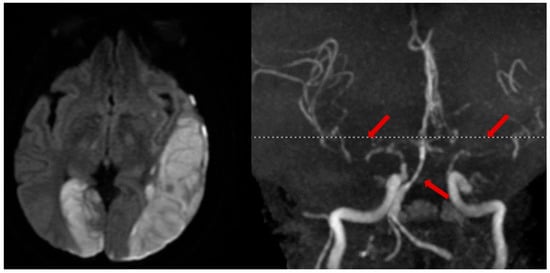

Traumatic brain injury (TBI) is a common diagnosis requiring acute hospitalization. Long-term, TBI is a significant source of health and socioeconomic impact in the United States and globally. The goal of clinicians who manage TBI is to prevent secondary brain injury. In this population, post-traumatic cerebral infarction (PTCI) acutely after TBI is an important but under-recognized complication that is associated with negative functional outcomes.